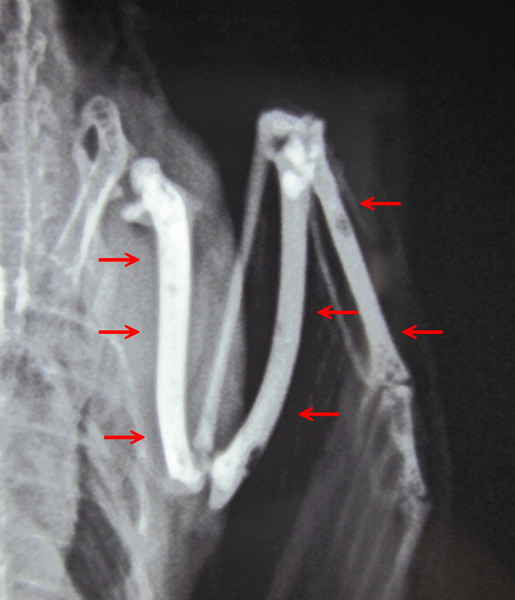

鳥類の骨の中は空洞で軽くできている(ハニカム構造)が、発情や代謝性疾患によって骨の中にカルシウムを貯蔵する。この骨の中にカルシウムが病的に過剰に沈着した状態を言う。英語でPolyostotic Hyperostosis(PH)とも言われる。別名「多骨性過骨症」。正常範囲の蓄積を「骨髄骨」、「髄様骨」と言う。